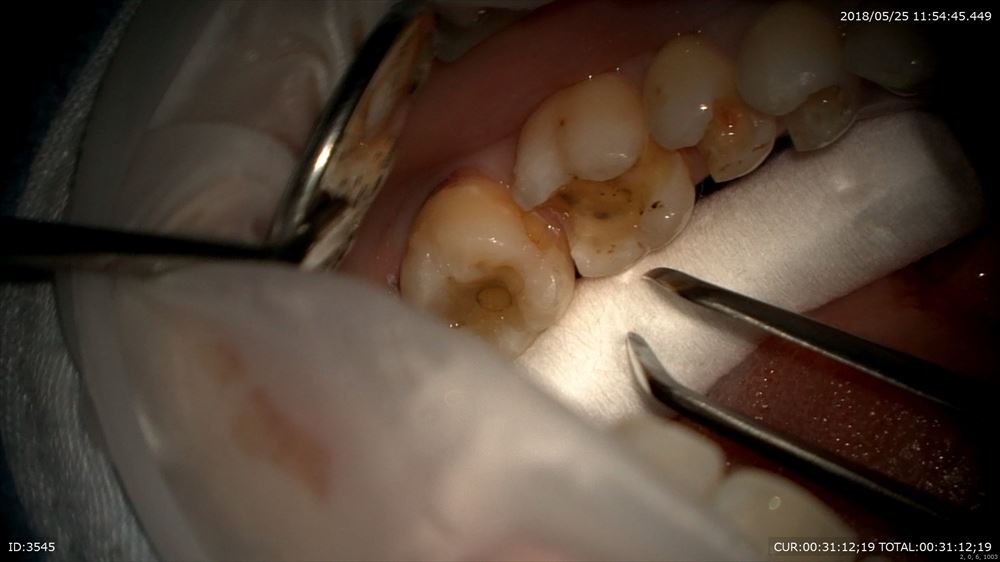

次のケースは左下に違和感があり咬むと痛い

咬むと痛いときはヒビやクラックが原因という事が多いです。金属の下の虫歯だけでなく

実はマイクロスコープを使用してこんな所を観察

ここにも原因があったのです。

ほら。患者さまにもこの画像を見て頂き

ここを拡大。クラック見てみましょう。20倍

この様に虫歯はクラックからも発生します。